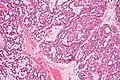

PLGAs consist of a monomorphous cell population that has a varied histologic morphology.

Microscopically, its histology can be confused with an adenoid cystic carcinoma and a pleomorphic adenoma.